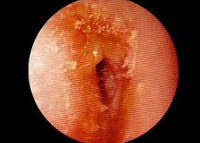

Отоскопия при ограниченном наружном отите обнаруживает наличие в слуховом проходе фурункула. В начальной стадии наружного отита фурункул имеет вид припухлости красного цвета. Созревший фурункул практически перекрывает слуховой проход, после его вскрытия отоскопия выявляет гной и наличие кратерообразного отверстия на вершине инфильтрата.

Выраженная болезненность при надавливании на козелок, оттягивании ушной раковины, пальпации в заушной области и над углом верхней челюсти свидетельствует о разлитом воспалении слухового прохода. Отоскопия при диффузном наружном отите обнаруживает тотальное покраснение и отечность кожного покрова, выстилающего слуховой проход, наличие эрозий с серозным отделяемым. В более позднем периоде наружного отита выявляется обтурация слухового прохода из-за выраженного отека его стенок, визуализируются язвы и трещины, выделяющие зеленовато-желтый гной. Аудиометрия свидетельствует о наличие тугоухости по кондуктивному типу. Латерализация звука происходит к больному уху. Бактериологическое исследование отделяемого из уха позволяет верифицировать возбудителя и установить его чувствительность к основным антибактериальным препаратам.

При наружном отите проход будет забит гнойными массами либо серозной жидкостью. Он немного сужен из-за воспаления тканей, стенки покраснели. Барабанная перепонка часто вовлекается в воспалительный процесс. При надавливании на кожу вокруг уха пациент отмечает усиление боли.